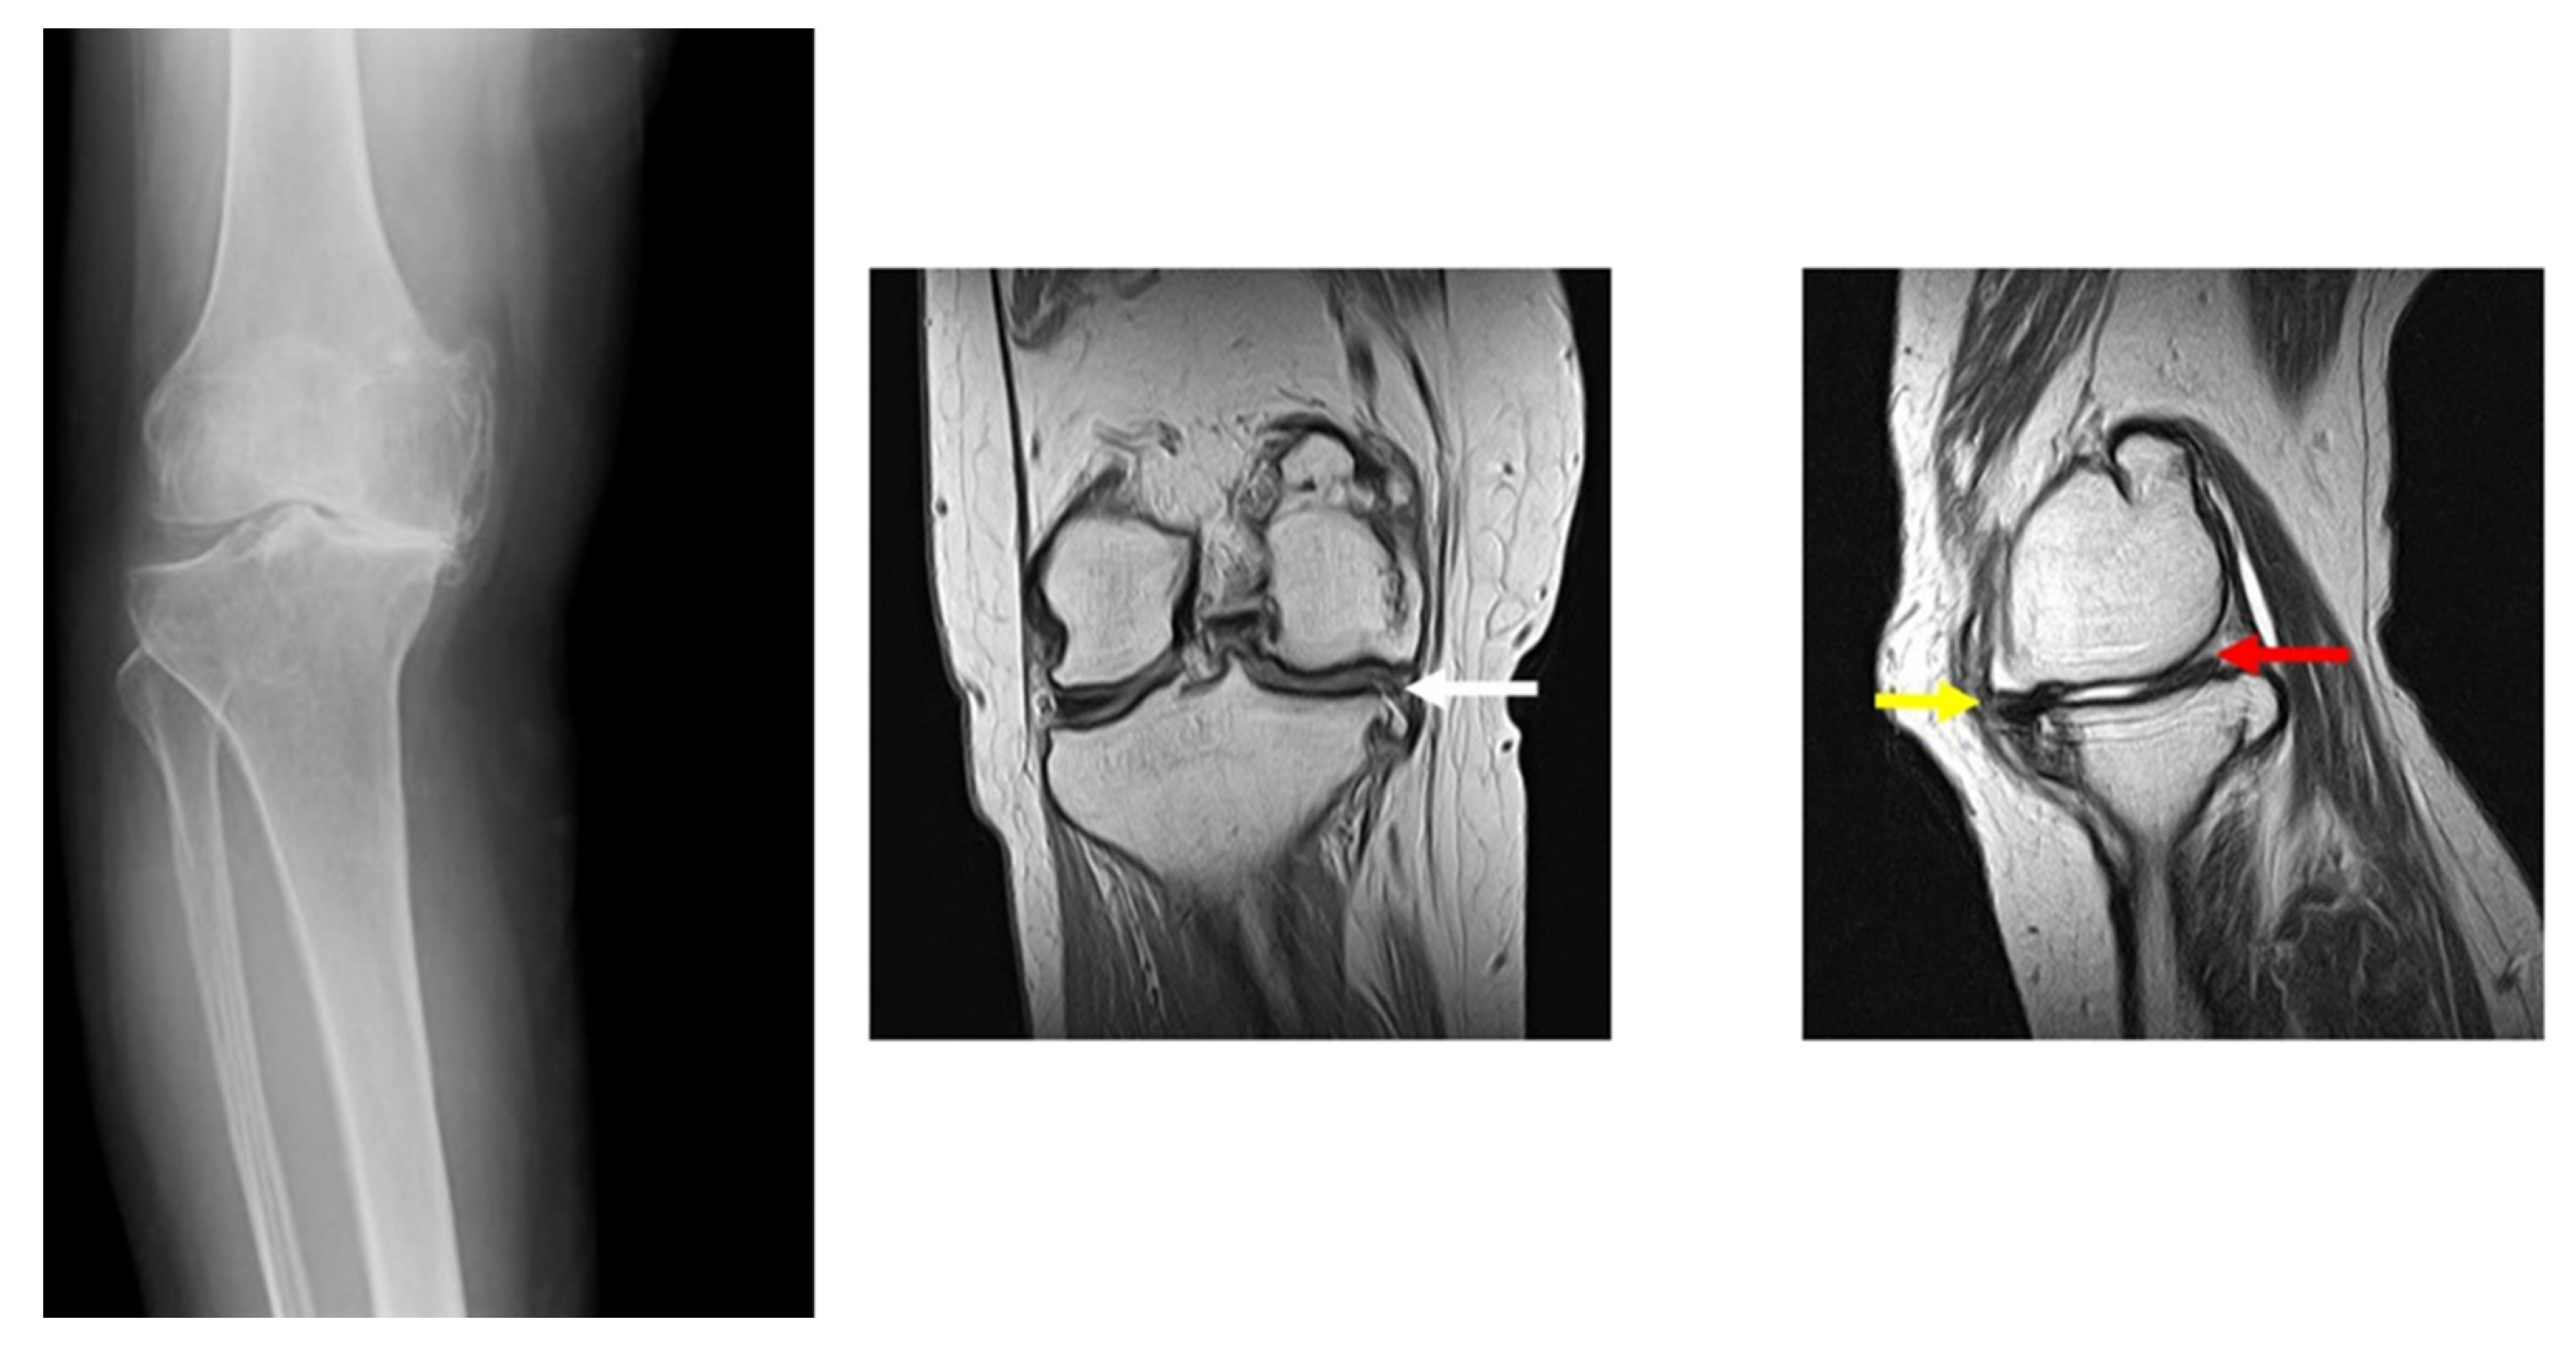

2.1. Subject